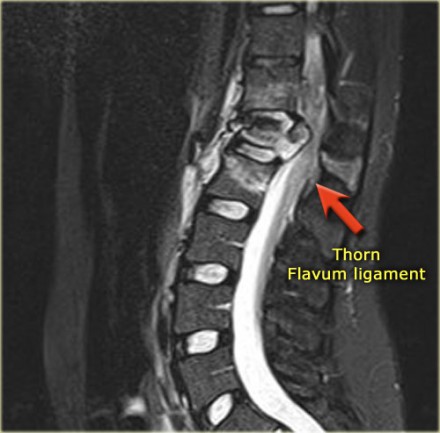

Look at the images.

What are the findings?

Then scroll to the next images.

The findings are:

- Vertebral bodies show marrow edema as a result of a fracture.

- Torn flaval ligament (yellow arrow).

- Fractures through the posterior elements (red arrows).

The TLICS-score is high, because there is distraction and injury to the PLC.